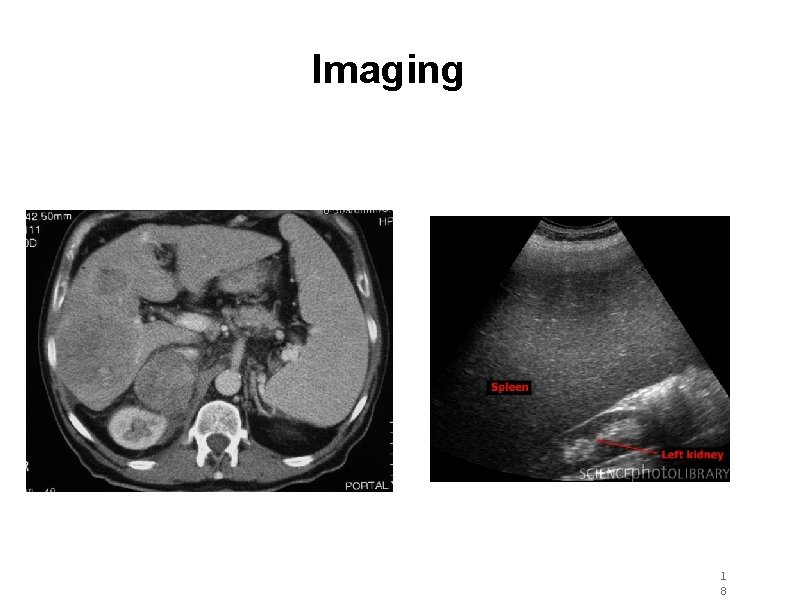

Splenomegaly http: //www. youtube. com/watch? v=u 0 ozq. FNCHKU 1 7

Imaging 1 8